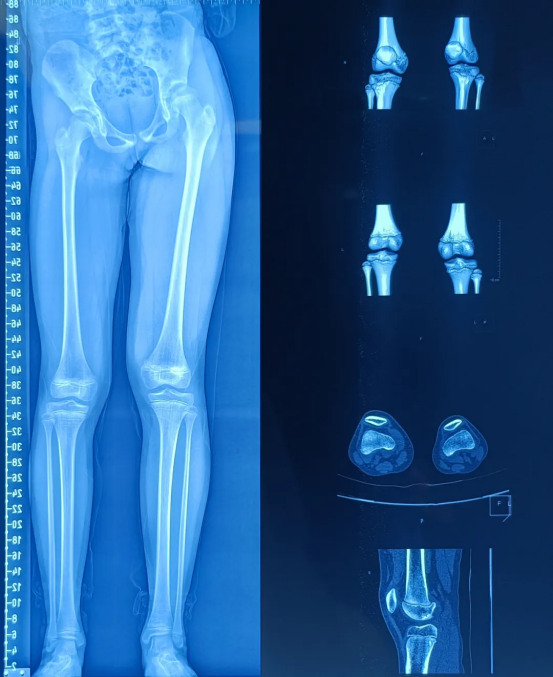

Screw placement is a critical step in the surgery. It requires accurate placement in specific epiphyseal regions of the femur and tibia, which not only achieves the growth inhibition effect but also avoids damaging healthy epiphyses, blood vessels, or nerves, imposing demanding exceptional surgical accuracy. When locating the target sites (such as the femur and tibia) , surgeons can clearly identify the position of the epiphyseal plate using Perlove Medical’s 3D C-arm. This helps them define the safe zones for drilling and screw insertion, establish an optimal relative relationship between the screws, epiphyses, and bone axes, and eliminate risks like screw deviation or bone penetration.

Intraoperative 3D images were acquired by the Perlove Medical’s 3D C-arm.

During the procedure, the positioning guidewire is inserted into the growth plate. A 3D scan is then performed by the 3D C-arm to confirm the guidewire's placement. Once verified, the plate is attached and secured with cannulated screws.